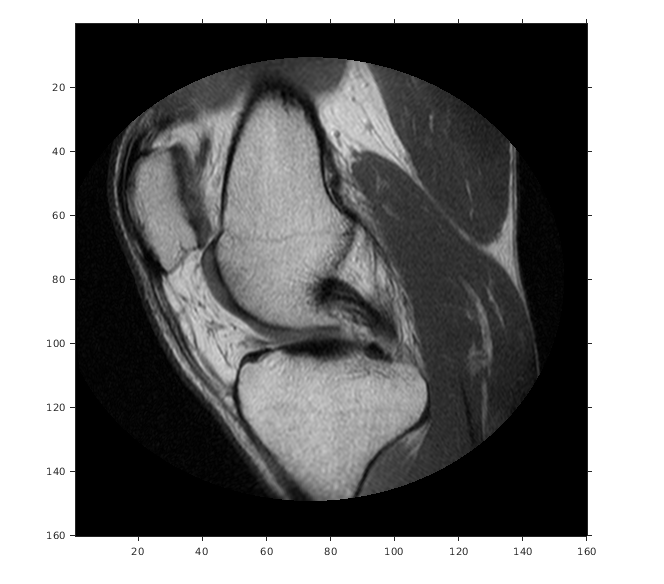

Считайте 2D полутоновое изображение колена в рабочую область.

m = dicominfo('knee1.dcm');

A = dicomread(m);Создайте imref2d объект, задавая размер и разрешение пикселей. Файл DICOM содержит поле метаданных PixelSpacing это задает разрешение изображения в каждой размерности в миллиметрах на пиксель.

Отобразите изображение, включая пространственный объект привязки. Координаты осей отражают мировые координаты. Заметьте, что координата (0,0) находится в левом верхнем углу.

figure

imshow(A,RA,'DisplayRange',[0 512])